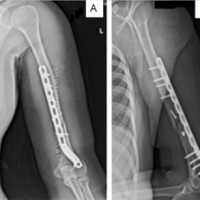

A 19-year-old male presented with bilateral hip pain and gait abnormality of 1 year’s duration. He had a prior history of steroid therapy for tuberculous meningitis. Magnetic resonance imaging (MRI) revealed bilateral AVN of the femoral heads (ARCO Stage II), and he was scheduled for bilateral core decompression with platelet-rich plasma injection (Fig. 1).

Figure 1: Post-operative X-ray.